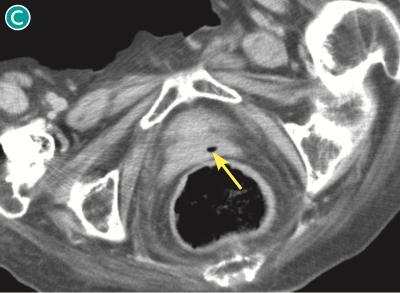

図 nonsurgical pneumoperitoneumの一例(単純CT,脂肪条件)

90歳代女性で発熱を主訴に来院.下腹部レベル(🅐)では,腸間膜を主体に複数の小さな腹腔内free air が認められる( ).骨盤部レベル(🅑,🅒)では,子宮( ![]() )および膣(

)および膣( ![]() )の腔内にもairが認められる.本例は消化管穿孔はなく,女性生殖器の感染により生じたairが腹腔内に移動したものと考えられた.

)の腔内にもairが認められる.本例は消化管穿孔はなく,女性生殖器の感染により生じたairが腹腔内に移動したものと考えられた.